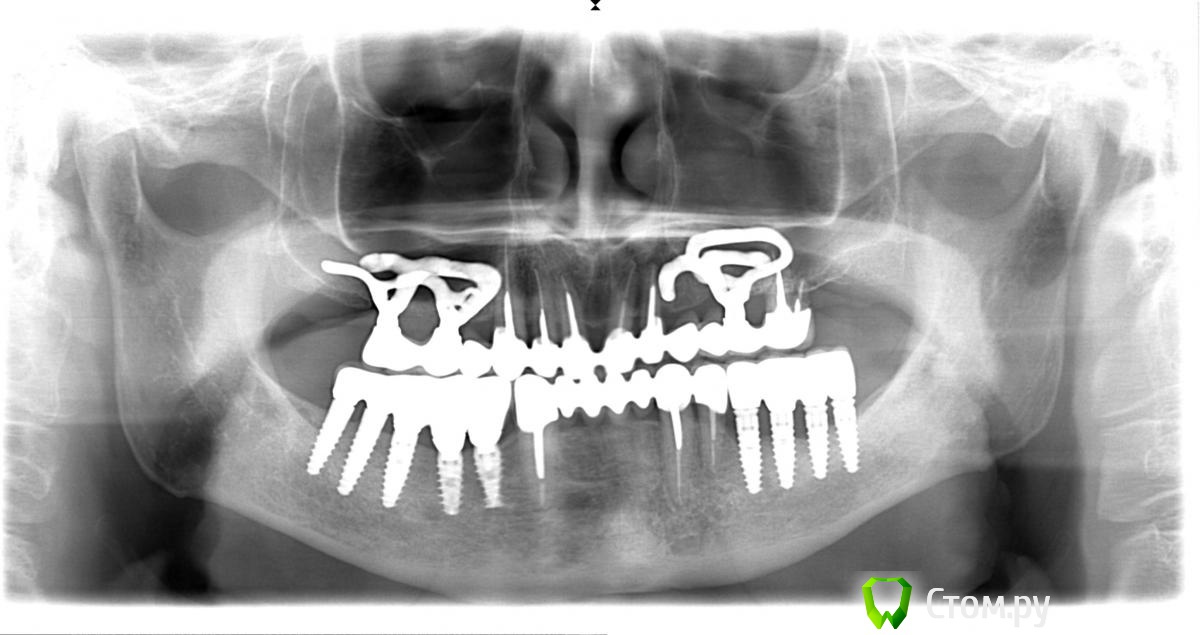

Troy Опубликовано 28 апреля, 2014 Поделиться Опубликовано 28 апреля, 2014 Вот такой рекольчик субпериостальников 5 лет прошло. Только камнями за НЧ кидать не надо . Это все таки моя глубокая молодость и за 5 лет мои взгляды сильно поменялись :). На синус пациент был категорически не согласен (интернет виноват),а хотел несъем2009 год2014 год. Жалоб нет. Так это выглядит сейчас. Ленты необнажены. Пардон за плохие фотки - фоткал на колегину мыльницуХотелось бы услышать Ваши комменты. 1 5 Ссылка на комментарий

red_butler Опубликовано 28 апреля, 2014 Поделиться Опубликовано 28 апреля, 2014 Да ну? Почему же?В третьем сегменте кость у имплантов ушла почти на 1/2, 2.7 удалять. Фото плохие, в Области 2.5 похоже свищ, резьба винтов тридцатой стороны выступает в полость рта и все в камнях. Мало? Ссылка на комментарий

Troy Опубликовано 28 апреля, 2014 Автор Поделиться Опубликовано 28 апреля, 2014 В третьем сегменте кость у имплантов ушла почти на 1/2, 2.7 удалять. Фото плохие, в Области 2.5 похоже свищ, резьба винтов тридцатой стороны выступает в полость рта и все в камнях. Мало?27 - его любимый зуб, он отказался его удалять еще 5 лет назад, пошли на поводу, пролечили покрыли, пока небеспокоит. В обл 25 свища нет, красное пятно артефакт на снимке фото плохие. Камней у него нет. Проблеммы в 3 сегменте действительно присутствуют. Но цель была показать СПИ.Извините что разачаровал .... :( А не новокузнецкие ли это "шедевры" ?Нет 1 1 Ссылка на комментарий

Mane Опубликовано 29 апреля, 2014 Поделиться Опубликовано 29 апреля, 2014 в третьем секторе еще до установки формирователя кость уже убежала от импланта?через 5 лет кость убежала везде 1 Ссылка на комментарий

Andex Опубликовано 2 мая, 2014 Поделиться Опубликовано 2 мая, 2014 Мне одному видится "недосадка" коронок в 3 сегменте? это могло явиться причиной такого объема ухода кости? 1 Ссылка на комментарий